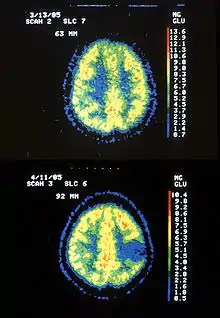

Two PET images—the upper of which shows a normal brain and the lower shows astrocytoma. | |